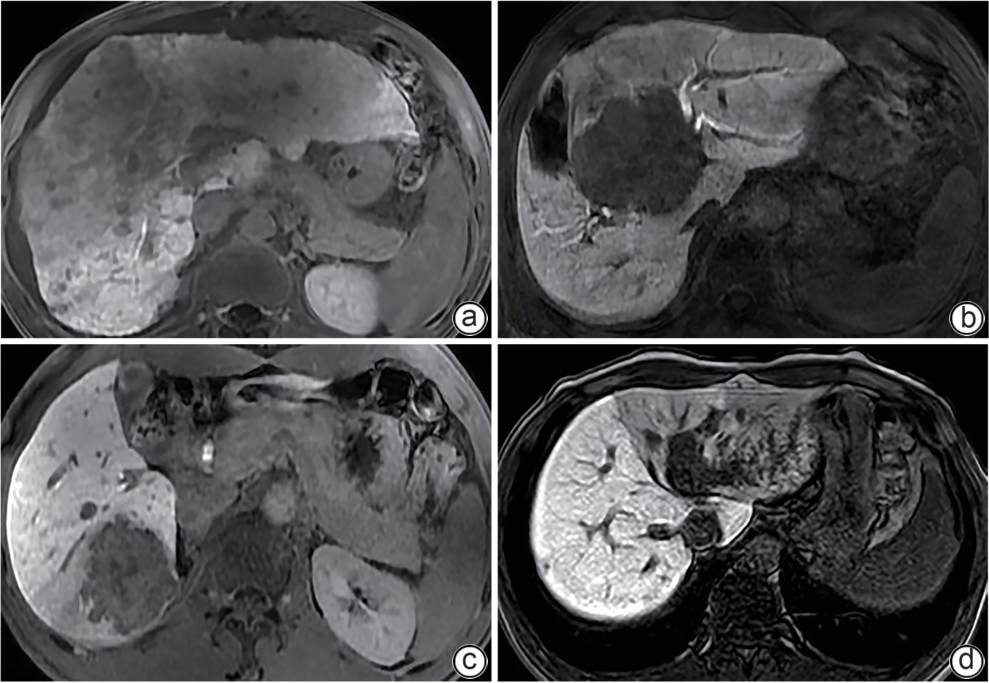

Primary splenic lymphoma misdiagnosed as Sjögren’s syndrome with liver cirrhosis: A case report

Chengcheng LI, Yuhong LIU, Lu WANG, Hong PENG, Xinhua LUO, Hong LI

2025, 41(9): 1883-1887. DOI: 10.12449/JCH250925

Abstract(464) HTML (106) PDF (5783KB)(65)

Abstract:

Primary splenic lymphoma is a rare malignant neoplasm, with similar clinical manifestations to Sjogren’s syndrome and liver cirrhosis, which often leads to misdiagnosis. This article reports a case of primary splenic lymphoma misdiagnosed as Sjogren’s syndrome with liver cirrhosis, in order to improve the understanding of primary splenic lymphoma, Sjogren’s syndrome, and liver cirrhosis and avoid misdiagnosis and treatment delay.